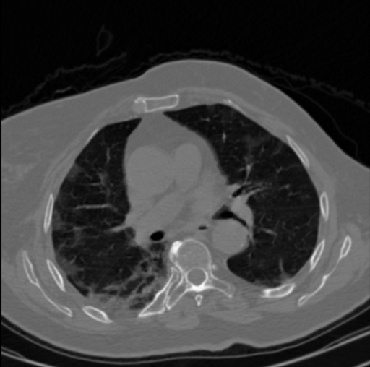

Early and reliable COVID-19 diagnosis based on chest 3-D CT scans can assist medical specialists in vital circumstances. Deep learning methodologies constitute a main approach for chest CT scan analysis and disease prediction. However, large annotated databases are necessary for developing deep learning models that are able to provide COVID-19 diagnosis across various medical environments in different countries. Due to privacy issues, publicly available COVID-19 CT datasets are highly difficult to obtain, which hinders the research and development of AI-enabled diagnosis methods of COVID-19 based on CT scans. In this paper we present the COV19-CT-DB database which is annotated for COVID-19, consisting of about 5,000 3-D CT scans, We have split the database in training, validation and test datasets. The former two datasets can be used for training and validation of machine learning models, while the latter will be used for evaluation of the developed models. We also present a deep learning approach, based on a CNN-RNN network and report its performance on the COVID19-CT-DB database.